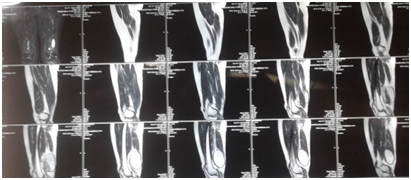

A 30 year old married female with no known comorbidity presented with a throbbing pain of moderate to severe intensity in left thigh and popliteal fossa region. On physical examination there was a tender erythematous, fluctuant swelling on posterior aspect of distal thigh and popliteal fossa. Incision and drainage of Abscess was done in one of the local hospitals and about 1.5 L of frank pus was drained. As per the records available with the patient. Pus contained some whitish membranes and cysts. Histopathological examination of specimen was done which revealed lamellated membranes of Echinococcus granulosus. No post-operative medical therapy was prescribed at that time. After a period of about one year the lady again presented to Sheri Kashmir Institute of medical Sciences Soura Srinagar with gradually increasing painless swelling in distal one third of thigh posteriorly. Ultrasonography of left thigh swelling was done which showed evidence of 10x4.7x6.2cm, thick walled cyst with finger-like projections and daughter cysts in lower third of posterior thigh with surrounding fat stranding, suggestive of hydatid Cyst. Screening ultrasonography of liver and spleen showed no cystic lesion. Chest Radiography was also found to be normal. MRI of Left lower thigh showed fluid intensity collection or cyst between Biceps femoris and semitendinosus myo-fascial planes which was extending deep to semitendinosus muscle. The swelling was 9.1x6.3x5.5cm and showed hypointense intracystic septae or crumpled membranes. Mild hypointense signal on T1W images and bright signal on STIR and T2W images was seen,suggestive of infected Hydatid Cyst. Hydatid Serology of the patient was found to be positive. Patient was put on oral Albendazole 400mg for 2 weeks and then excision of cyst was done. Albendazole was continued postoperatively for 4 weeks (Figure 1), (Figure 2).

Figure 2 MRI showing large cyst with crumpled scolices inside between biceps femoris and semitendinosus.